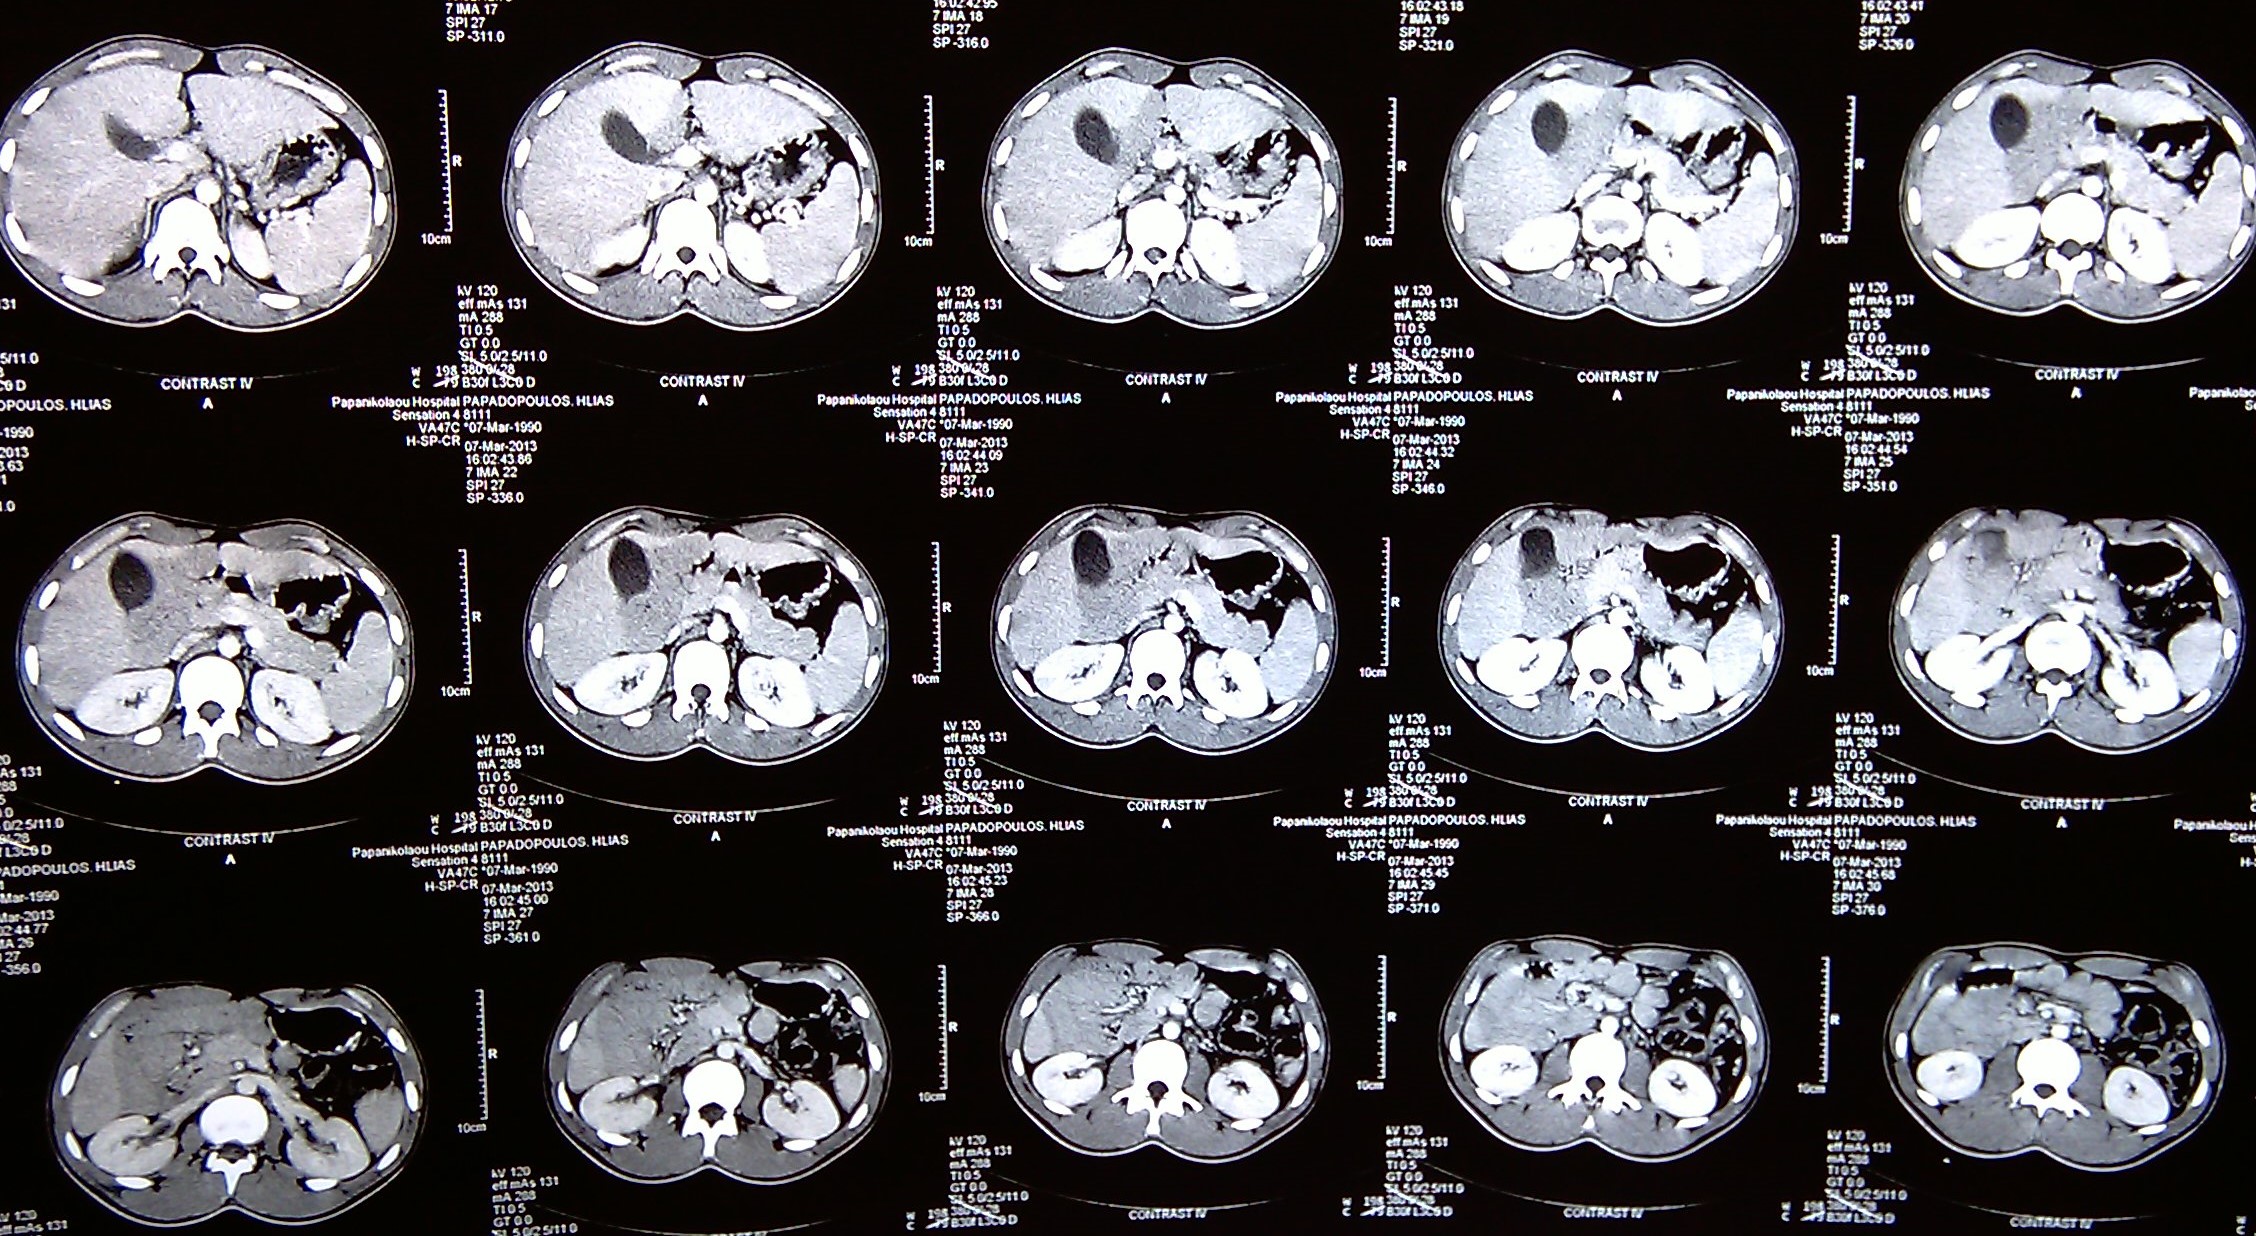

CT άνω κοιλίας με σκιαγραφικό που αναδεικνύει συστάδα διατεταμένων ελίκων λεπτού εντέρου στο κέντρο δίνοντας εικόνα κουνουπιδιού (βέλη) (Ευγενική παραχώρηση Dr. V. Penopoulos)